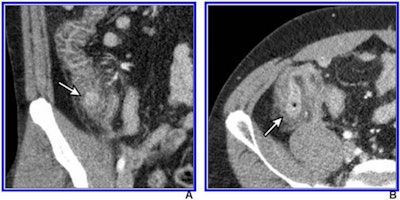

The results could help clinicians better distinguish right colonic diverticulitis from appendicitis, noted a team led by Dr. Hae Young Kim, PhD, of Seoul National University Bundang Hospital in South Korea.

Kim and colleagues performed a study that included 3,074 patients between the ages of 15 and 44 seen at 20 hospitals. The patients were randomized into two groups, one that underwent contrast-enhanced 2-mSv CT (1,535) and another that underwent conventional CT (1,539) between December 2013 and August 2016. A team of 161 radiologists read the exams, recommending alternative diagnoses in 976 of the low-dose CT exams and in 924 of the conventional CT exams.